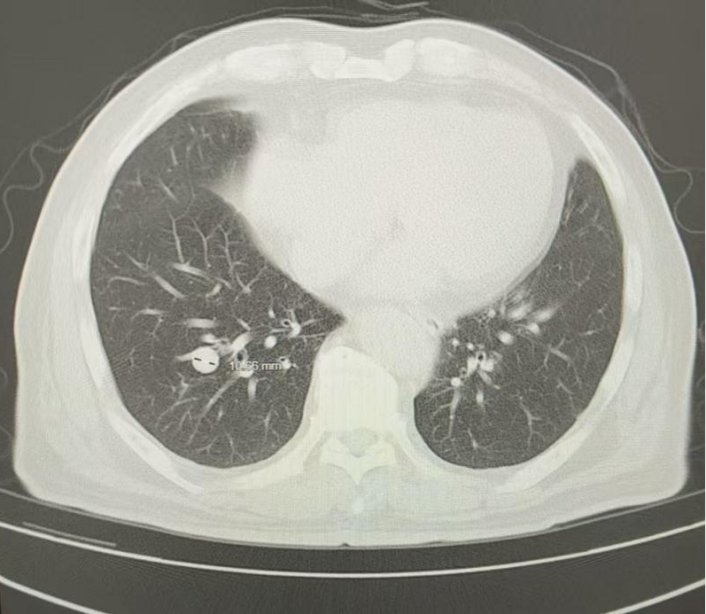

2024年9月(治疗后5个月),复查胸部CT:两肺多发结节,转移灶首拟,对比2024.6.17老片,两肺结节大致相仿,疗效评估为PR

图3 患者治疗后5个月胸部影像学图像(2024年9月23日)

2024年12月(治疗后8个月),复查胸部CT:两肺多发结节,转移灶首拟,对比2024.09.23老片,右下肺结节似略增大,疗效评估为疾病稳定(SD)

图4 患者治疗后8个月胸部影像学图像(2024年12月16日)